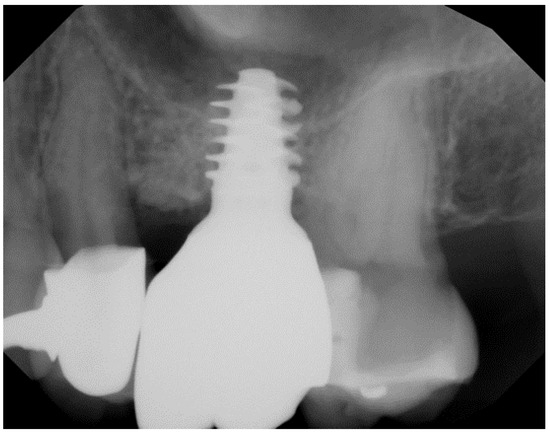

- Pirker, W.; Kocher, A. Immediate, non-submerged, root-analogue zirconia implant in single tooth replacement. Int. J. Oral Maxillofac. Surg. 2008, 37, 293–295. [Google Scholar] [CrossRef]

- Pirker, W.; Kocher, A. Immediate, non-submerged, root-analogue zirconia implants placed into single-rooted extraction sockets: 2-year follow-up of a clinical study. Int. J. Oral Maxillofac. Surg. 2009, 38, 1127–1132. [Google Scholar] [CrossRef]

- Pessanha-Andrade, M.; Sordi, M.B.; Henriques, B.; Silva, F.S.; Teughels, W.; Souza, J.C.M. Custom-made root-analogue zirconia implants: A scoping review on mechanical and biological benefits. J. Biomed. Mater. Res. B Appl. Biomater. 2018, 106, 2888–2900. [Google Scholar] [CrossRef]

- Pirker, W.; Wiedemann, D.; Lidauer, A.; Kocher, A.A. Immediate, single stage, truly anatomic zirconia implant in lower molar replacement: A case report with 2.5 years follow-up. Int. J. Oral Maxillofac. Surg. 2011, 40, 212–216. [Google Scholar] [CrossRef]

- Van Dooren, E.; Calamita, M.; Calgaro, M.; Coachman, C.; Ferencz, J.L.; Pinho, C.; Silva, N.R. Mechanical, biological and clinical aspects of zirconia implants. Eur. J. Esthet. Dent. 2012, 7, 396–417. [Google Scholar] [PubMed]

- Regish, K.M.; Sharma, D.; Prithviraj, D.R. An overview of immediate root analogue zirconia implants. J. Oral Implantol. 2013, 39, 225–233. [Google Scholar] [CrossRef] [PubMed]

- Mangano, F.G.; De Franco, M.; Caprioglio, A.; Macchi, A.; Piattelli, A.; Mangano, C. Immediate, non-submerged, root-analogue direct laser metal sintering (DLMS) implants: A 1-year prospective study on 15 patients. Lasers Med. Sci. 2014, 29, 1321–1328. [Google Scholar] [CrossRef]

- Akkoyun, E.F.; Demirbas, A.E.; Gumus, H.O.; Alkan, B.A.; Alkan, A. Custom-made root analog immediate dental implants: A prospective clinical study with 1-year follow-up. Int. J. Oral Maxillofac. Implants 2022, 37, 1223–1231. [Google Scholar] [CrossRef]